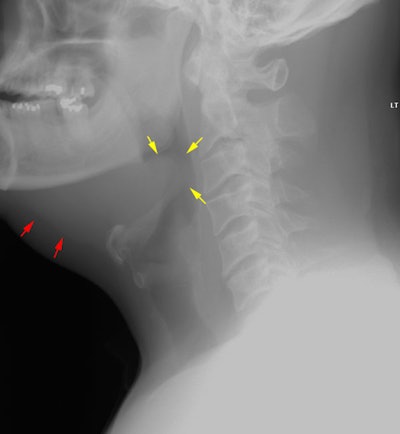

Angioneurotic Edema:

Following initiation on antibiotic therapy, this patient presented with repiratory distress. The lateral soft tissue airway exam demonstrated marked enlargement of the epiglotis (yellow arrows) and submandibular soft tissue swelling (red arrows).